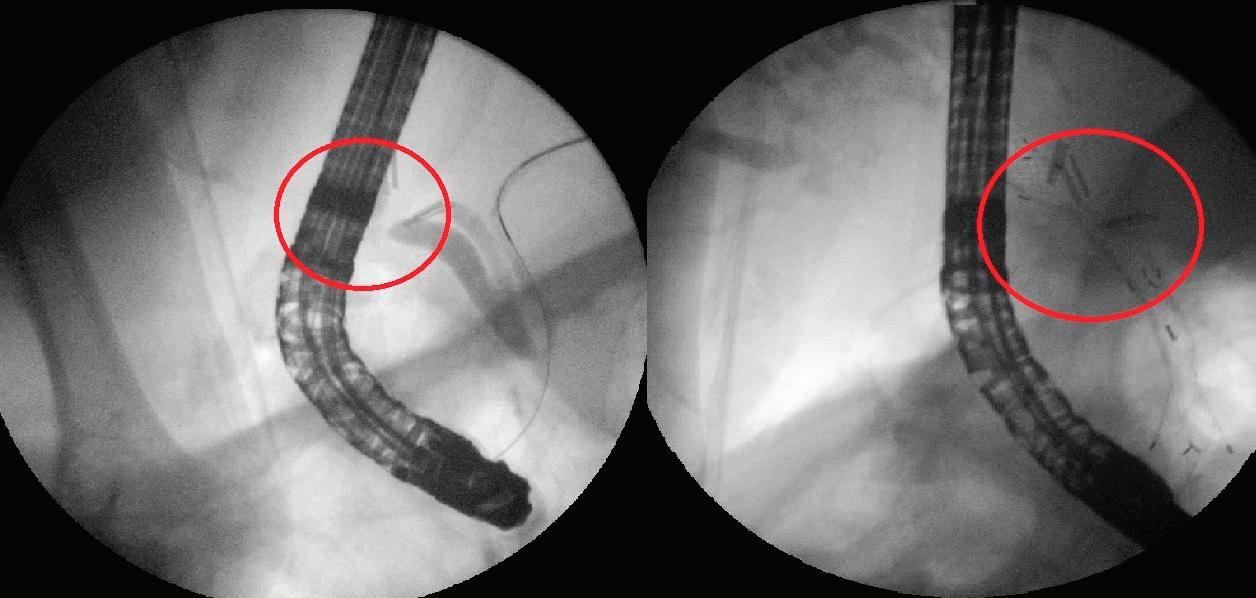

Фиг. 6 Ехоендоскопска холедо ходуоденостомия с ме тален частично покрит стент: А - ориентация на върха на апарата към чернодробния хилус, пункция и контрастира не на жлъчното дърво; В - въвеждане на водач, дилатация на тракта; Странсдуоденален стентфлуороскопски аспект; D - трансдуоденален стент - ендоскопски аспект

Ехоендоскопски билиарен дренаж (EUS-BD) Ендоскопската ретроградна холан гиопанкреатография (ЕРХПГ) е терапевти чен подход на първи избор при пациенти с билиарна обструк ция. При редица кли нични сценарии, оба че, процедурата е технически неуспеш

хирургично проме нена анатомия, ту

морна инфилтрация на Папила Фатери, малигнена дуоденал на обструкция, го лям перипапиларен дивертикул и дру ги. В миналото един ствени алтернативи при тези състояния са били перкутан ният билиарен дре наж или хирургични ят „байпас“. И двете техники са свързани с висок морбидитет, морталитет и про дължителен болни чен престой. Пер кутанният дренаж е свързан с лошо ка чество на живот и честа необходимост

първото пред

нар. „рандеву“, ехоендоскопско антеградно стентиране или ехоендоскопско създаване на билиодигестивна анастомоза - ехоендос копска хепатикогастростомия или холедохо дуоденостомия (Фиг. 6). Достъпът може да бъде трансгастрален - интрахепатален или трансдуоденален - екстрахепатален. Наличи ето на различни подходи дава възможност за избор на техника, конкретно адаптирана към индивидуалните анатомични особености на пациента[4]

Всички ехоендоскоопски билиарни дренаж ни интервенции са технически трудни и пред ставляват сериозно предизвикателство за ендоскопистите. Използването на LAMS при холедоходуоденостомия прави процедура та по-лесна и с по-нисък риск от усложнения. Методиката демонстрира отлична ефектив ност и безопасност и е с претенции да за мени ЕРХПГ като процедура на първи избор при дистални малигнени билиарни обструк ции[14,15]. Ехоендоскопска гастроентеростомия Itoi et al. публикуват първото проспективно проучване с 20 пациенти, при които е напра вена ехоендоскопска гастройеюноанастомо